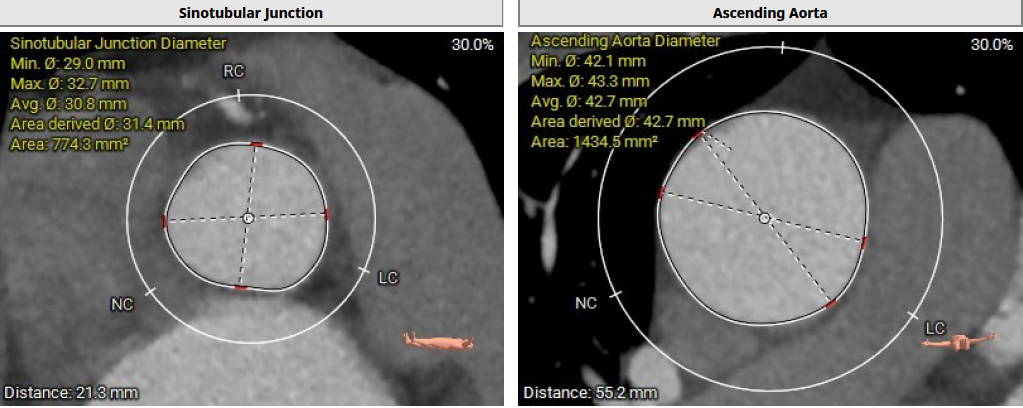

患者Type1 二叶瓣,右无融合,融合嵴钙化,钙化主要分布瓣叶缘和融合嵴处,无冠窦底钙化向下延伸至流出道4mm处。Annulus面积398mm²,LVOT面积400mm²,SOV 27.6-30.9mm,STJ高度21.3mm,内径29-32.7mm,瓣环角度62°,升主动脉扩张,左冠高度14.9mm,左冠瓣叶长度15.7mm,右冠高度15.8mm,右冠瓣叶长度9.2mm,模拟植入21#瓣膜VTC LCA 2.4mm,右侧髂内分叉处可见钙化,右侧髂外动脉最细为6.1mm,左侧髂外动脉最细为6.1mm,外周入路尚可。

窦宽:Distance L:30.9mm Distance R:27.6mm Distance N: 28.2mm

窦管交界:Area: 774.3mm² 、Mean Diameter:30.8mm;升主:Area: 1434.5mm²;Mean Diameter:42.7mm

850阈值下钙化积分为267mm³,钙化主要分布瓣叶缘和融合嵴,无冠窦底钙化向下延伸至流出道4mm。